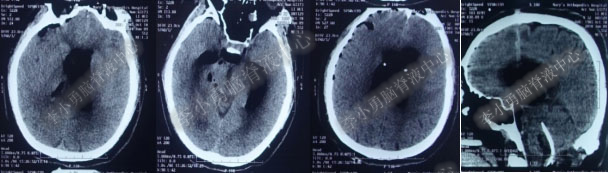

入院第22天即2018年5月6日(第3次软性内镜术后19天),患者意识昏睡,发热,复查头部CT(图-15)全脑室系统又扩大。

图-15:2018年5月6日复查头部CT

入院第38天即2018年 5月22日(第3次软性内镜术后35天),复查头部CT(图-16)显示侧脑室、四脑室仍扩张。

图-16:2018年 5月22日头部CT

入院时:慢性病态,体温高达38.9°C,昏睡,双侧眼球内聚,带脑室腹壁外引流管状态,脑脊液透明但色黄(图-17)。

图-17:2018年5月23日入院状态

图-18:2018年5月23日入院时头部CT